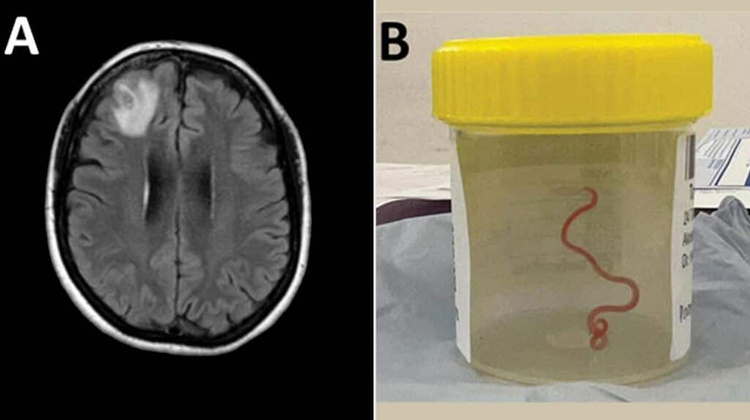

Инфекционист Санджай Сенанаяке (Sanjaya Senanayake) как обычно работал в больнице в Канберре, когда ему позвонил коллега и сообщил: «Боже мой, ты не поверишь, что я только что обнаружил в мозге этой женщины. Он живой и извивается». Так, врачи вытащили из пациентки паразитического круглого червя длиной 8 см. Разбираемся, откуда в мозге взялся паразит и что будет с женщиной.

64-летняя женщина из Нового Южного Уэльса впервые поступила в местную больницу в конце января 2021 года после трех недель болей в животе и диареи. Симптомы сопровождались постоянным сухим кашлем, лихорадкой и ночной потливостью. К 2022-му добавилась забывчивость и депрессия, что послужило поводом для направления в больницу Канберры. МРТ головного мозга выявила нарушения, требующие хирургического вмешательства, — ученые обнаружили паразита.

Поиски оказались безрезультатными, и они позвали на помощь сторонних специалистов, отправив еще живого червя в лабораторию паразитологов. Те выяснили, что перед ними Ophidascaris robertsi.